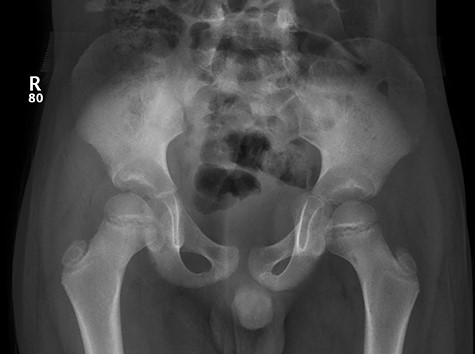

CT hips reported a well-defined lesion seen bilaterally in the neck of femur anterior infero-medial aspect, more prominent on the left side measuring 7 x 3 mm on left side both in coronal (Fig. 3) and axial (Fig. 4) views. On the right side, other lesion measuring 2 x 1 mm (Fig. 5) seen in coronal view. These two lesions are well defined with a sclerotic border with a small cortical defect. The lesion shows fat density. The symmetrical appearance of the lesion combined with the fat density and location suggest the diagnosis of synovial herniation pit. MRI Pelvis revealed minimal left hip joint effusion with loculated fluid seen along the trochanteric bursa with the largest measuring 0.9 x 1.5 cm (Fig. 6, 7).

Sowed coronal cut of CT hips demonstrating the synovial pit on left and right side.

Follow-up X-ray showed regression of the lesion in the form of progression of the dense sclerosis of the defect of the left femur while the right femur neck lesion is barely visible (Figure 10) and advised for watchful waiting.